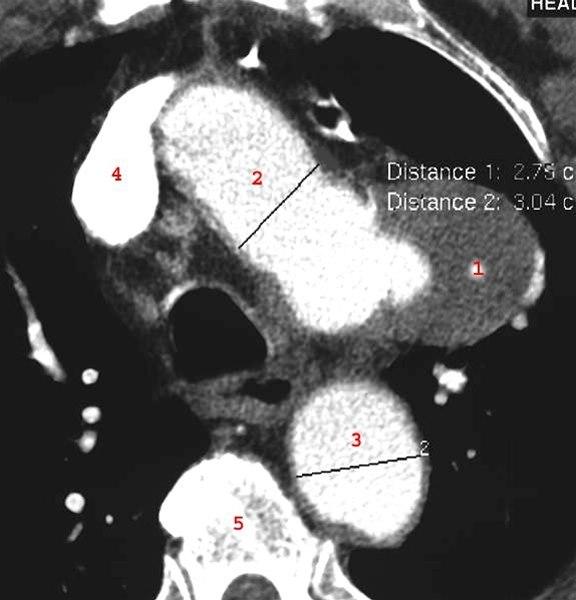

CT axialbilde med i.v. kontrast

Sacculært aneurisme på arcus aorta

Det meste av aneurismet er trombosert (1)

- Trombosert aneurisme

- Arcus aorta

- Aorta descendens

- Vena cava superior

- Ryggvirvel